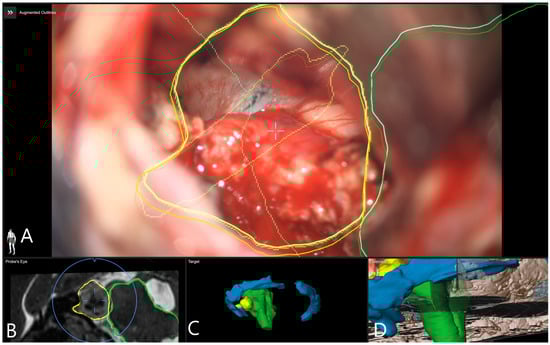

Illustrative Cases